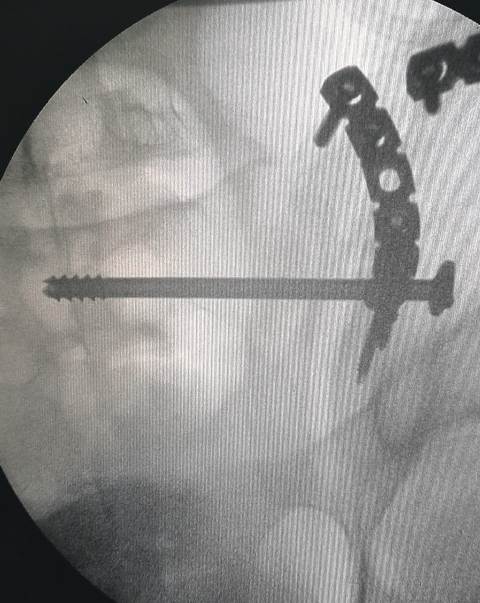

قام الفريق الطبي بقسم جراحة العظام بمستشفي الزقازيق العام، بقيادة الدكتور محمد راشد رئيس القسم، والدكتور أحمد عبدالسلام أخصائي جراحة العظام، والدكتور أحمد نوفل طبيب جراحة العظام، تحت إشراف الدكتور جلال بليغ مدير المستشفى، بإجراء جراحة متقدمة ذات طابع خاص للمرة الأولى بالمستشفى، لتثبيت كسر بمفصل الحوض والفقرات العجزية من خلال فتح أمامي، لمريض يبلغ من العمر ٢٧ عاما، مع تثبيت مغلق للمفصل الحرقفي العجزي له تحت جهاز الأشعة، وذلك بعد إجراء كافة الفحوصات الطبية والأشعات اللازمة للمريض، قبل إجراء العملية الجراحية له، والتي تمت بفضل الله بنجاح، والمريض الآن بحالة جيدة ومستقره، ويتلقي العلاج اللازم بقسم جراحة العظام تحت متابعة الأطباء بالمستشفي.